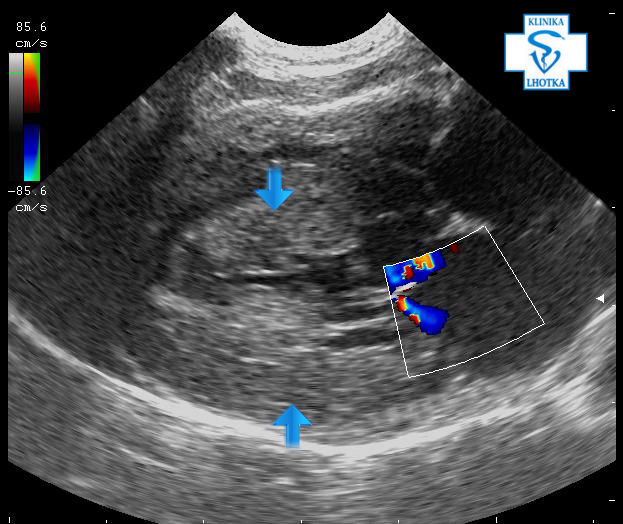

Na ultrasonografu  je možné „ztluštění“ srdeční svaloviny posoudit a změřit. Na podélném zobrazení srdce ukazují šipky na značně zbytnělou mezikomorovou přepážku a zadní stěnu levé komory:

Echokardiografie-HCM-dlouhá osa